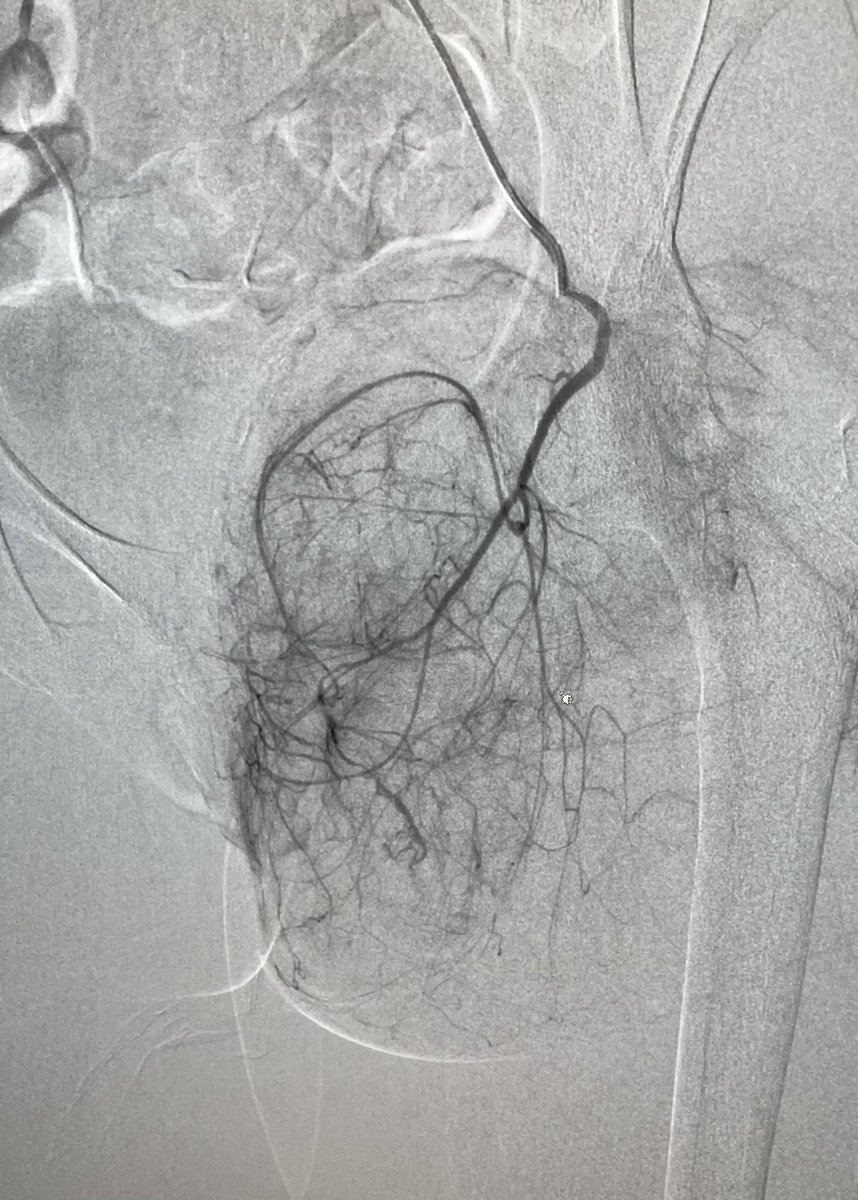

About 1/3 of our traumas involve the pelvis, here the left superior gluteal artery is bleeding from multiple branches. After embolization, hg stabilized and vitals improved.